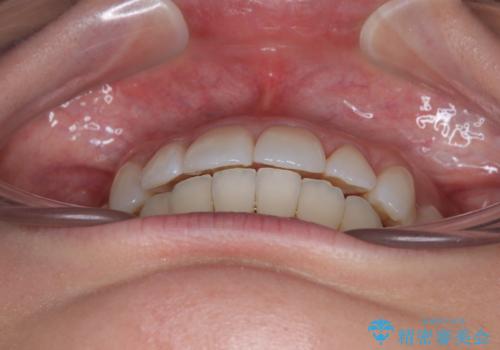

上下前歯のデコボコ ワイヤー装置で楽ちん矯正治療

矯正治療後には奥歯の銀歯やむし歯をセラミックやゴールドにて治療を行い、大変整った口腔環境へと改善さ。れました